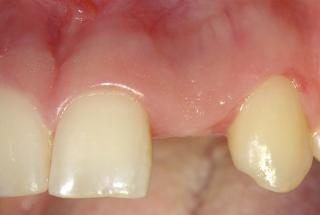

Clinical cases

MPI closely monitors clinical cases in the market to ensure their correct functioning and successful outcome.